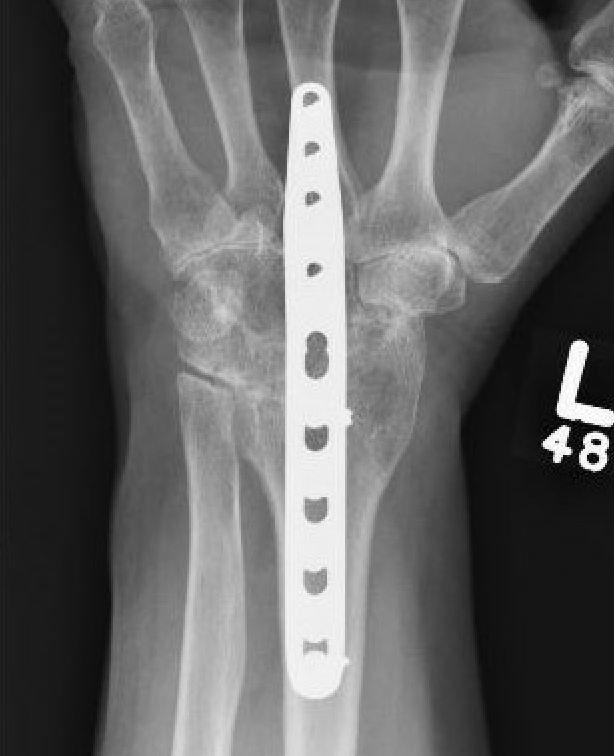

Spanning dorsal plate

Distal radius to third metacarpal

- fusion radiocarpal & midcarpal +/- fusion of 3rd carpometacarpal joint

- low profile and precontoured plate

- 15 degree dorsal angulation and slight ulna deviation to maximize grip strength

Dorsal plate